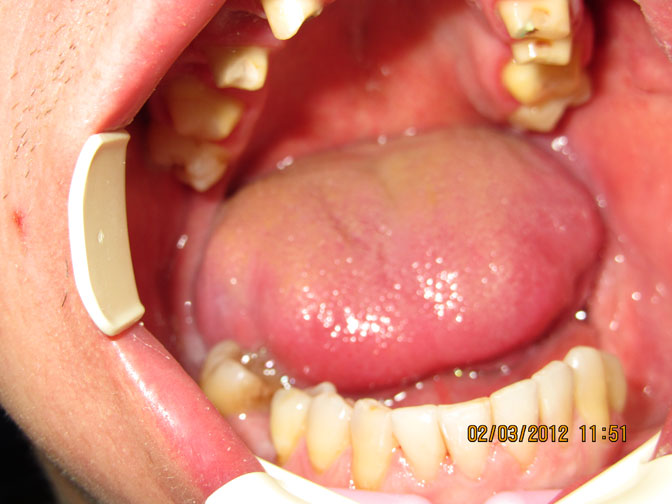

Фото №2,№3,№4 Зубы нижней челюсти проелечены. Восстановлена анатомическая форма зубов пломбировочными материалами.